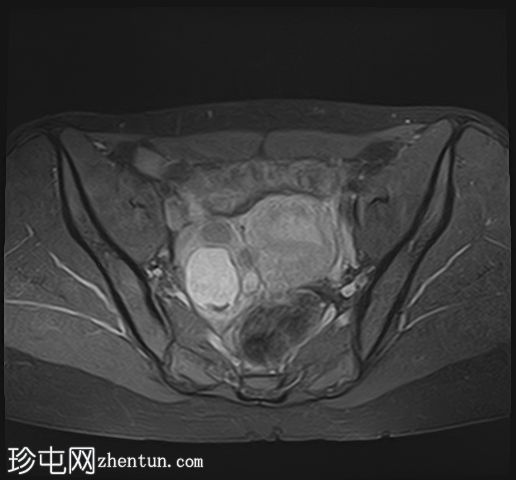

轴位T1加权像

脂肪抑制像

在右侧附件区可见一较大病灶,最大轴位和头尾径约为3 x 3.8 x 3.7 cm。该病灶在T1加权像上呈高信号,脂肪抑制像上无信号抑制,在T2加权像上呈低信号(阴影效应)。病灶壁可见T2暗点征结节,增强扫描后未见明显强化。

右侧附件区可见两个较小的类似病灶,最大径约1.2 cm。

此外,右侧附件区可见一扩张的管状结构,最大轴向和头尾径约6.3 x 2.1 x 5.2 cm。

该结构T1呈低至中等信号,T2呈高信号,分隔不完整。增强扫描未见明显强化,符合输卵管积水表现。

所描述的右侧附件病灶具有典型的子宫内膜异位囊肿MRI特征,包括T1高信号(无脂肪抑制)和T2低信号(阴影)。T2暗点征的存在进一步支持慢性出血性内容物。

相关的较小病灶可能代表其他子宫内膜异位种植灶。

扩张的管状结构伴有T2高信号和不完全分隔,符合输卵管积水的表现,输卵管积水常见于盆腔子宫内膜异位症。少量邻近游离液体通常为反应性积液。